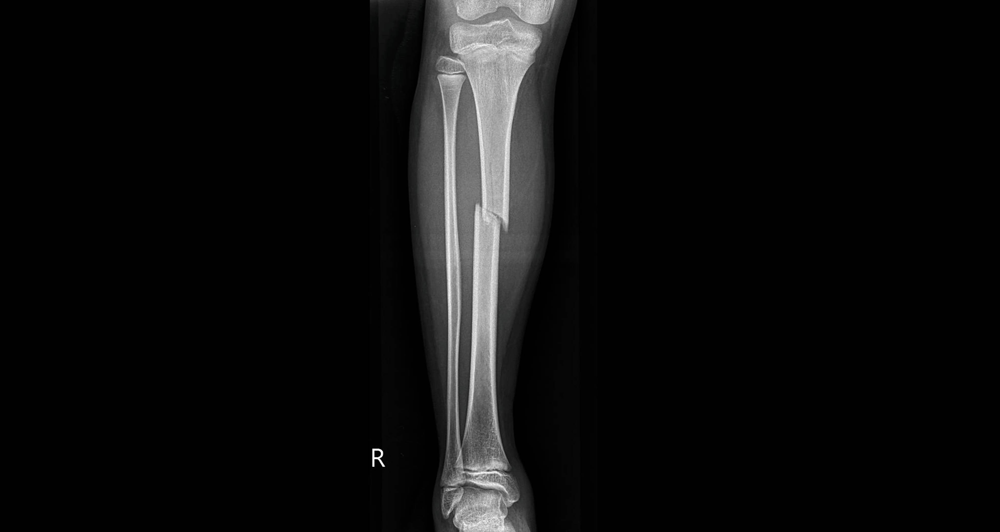

Traumatologische operative Therapie

Die traumatologische operative Therapie umfasst die Diagnostik und chirurgische Behandlung von akuten Verletzungen des Bewegungsapparates. Dazu zählen Knochenbrüche, Gelenkverletzungen, Band- und Sehnenverletzungen infolge von Unfällen oder Stürzen.